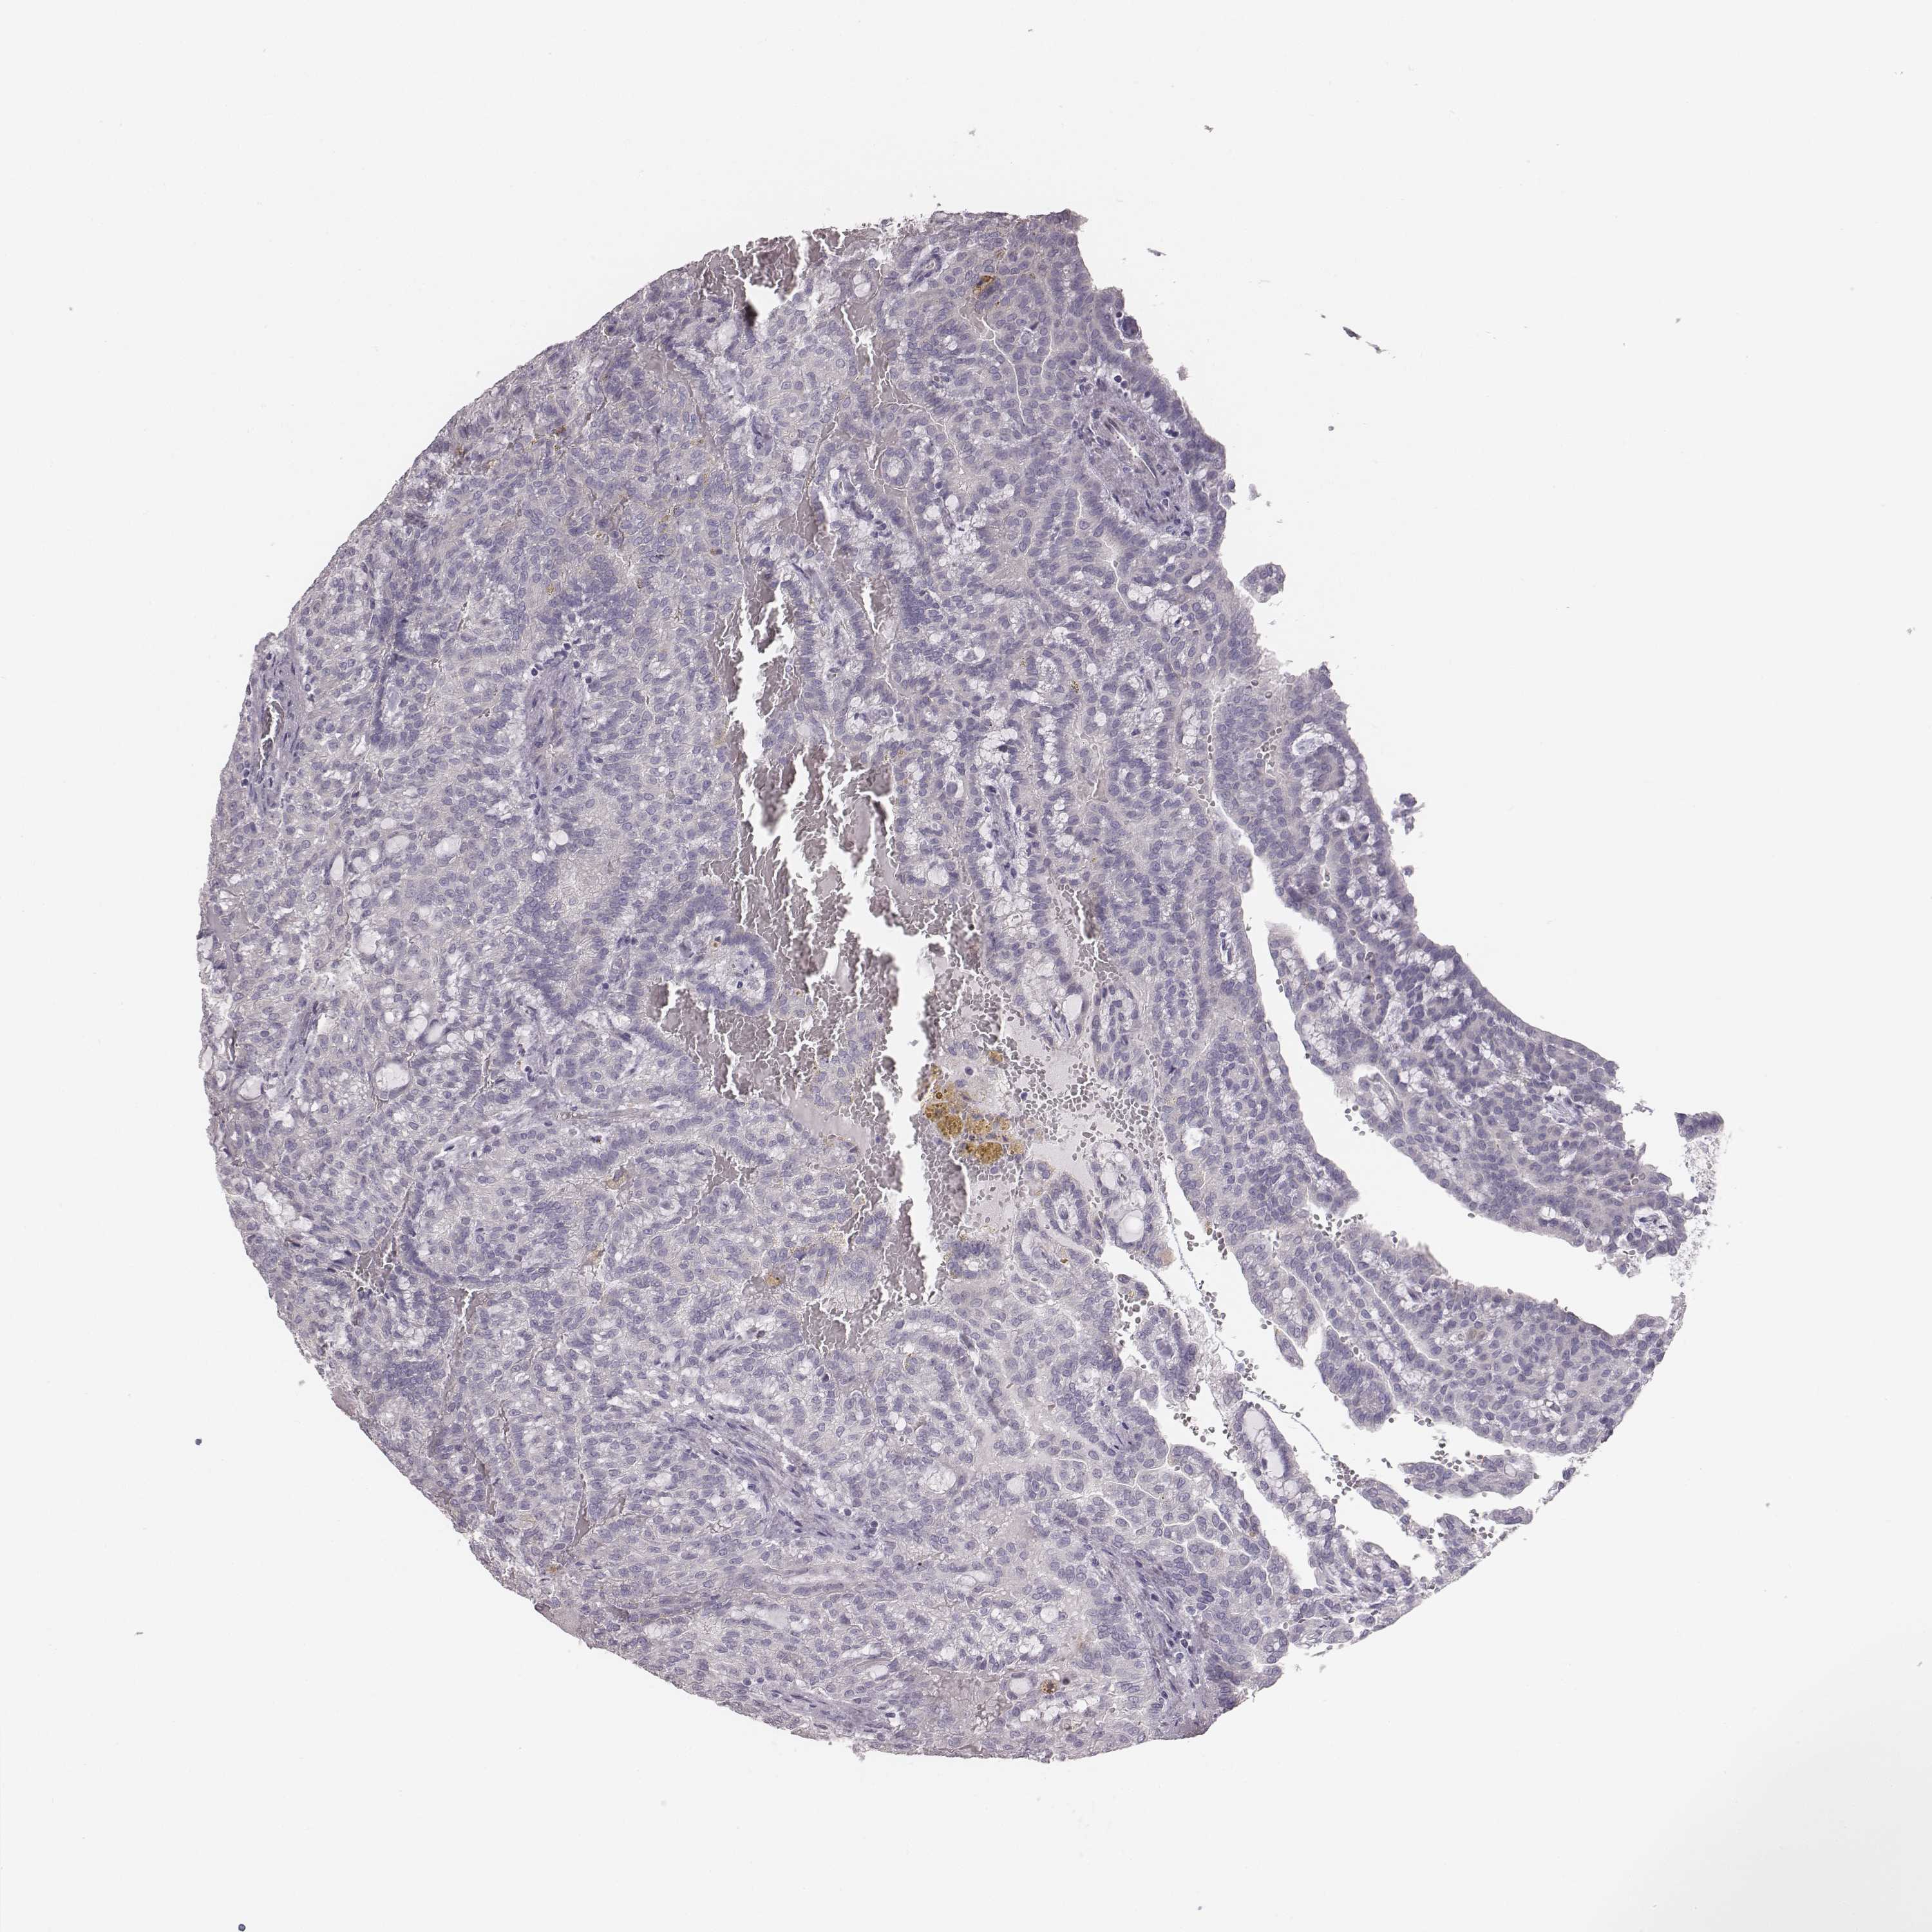

KIDNEY CHROMOPHOBE (TCGA) - Interactive survival scatter ploti

The Survival Scatter plot shows the clinical status (i.e. dead or alive) for all individuals in the patient cohort, based on the same data that underlies the corresponding Kaplan-Meier plots. Patients that are alive at last time for follow-up are shown in blue and patients who have died during the study are shown in red.

The x-axis shows the expression levels (FPKM) of the investigated gene in the tumor tissue at the time of diagnosis. The y-axis shows the follow-up time after diagnosis (years). Both axes are complimented with kernel density curves demonstrating the data density over the axes. The top density plot shows the expression levels (FPKM) distribution among dead (red) and alive patients (blue). The right density plot shows the data density of the survived years of dead patients with high and low expression levels respectively, stratified using the cutoff indicated by the vertical dashed line through the Survival Scatter plot. This cutoff is automatically defined based on the FPKM cutoff that minimizes the p-score. The cutoff can be changed by dragging the vertical line or by entering a cutoff value in the square labeled "Current cut-off".

Under the Survival Scatter plot the p-score landscape (black curve; left axis) is shown together with dead median separation (red curve; right axis). Dead median separation is the difference in median mRNA expression between patients who have died with high and low expression, respectively. It is calculated as follows: median FPKM expression of dead patients with high expression - median FPKM expression of dead patients with low expression. This is intended to aid the user in visually exploring custom cutoffs and the associated p-scores and dead median separation.

Individual patient data is displayed and can be filtered by clicking on one or more of the category buttons on the top of the page. Categories describing expression level and patient information include: high, low, alive, dead, female, male and tumor stages. The scale of the x-axis can be toggled between linear and log-scale by clicking on the "x log" button. Mouse-over function shows TCGA ID, patient information and mRNA expression (FPKM) for each patient.

& Survival analysisi

Kaplan-Meier plots summarize results from analysis of correlation between mRNA expression level and patient survival. Patients were divided based on level of expression into one of the two groups "low" (under cut off) or "high" (over cut off). X-axis shows time for survival (years) and y-axis shows the probability of survival, where 1.0 corresponds to 100 percent.

PBK is potential prognostic, high expression is unfavorable in Kidney Chromophobe (TCGA)

Best expression cut offi

: 3.47

TCGA RNA samplesi

RNA-seq data is reported as average FPKM (number Fragments Per Kilobase of exon per Million reads), generated by the The Cancer Genome Atlas (TCGA) .

Normal distribution across the dataset is visualized with box plots, shown as median and 25th and 75th percentiles. Points are displayed as outliers if they are above or below 1.5 times the interquartile range. FPKM values of the individual samples are presented next to the box plot.

Average pTPM 2.5

Number of samples 64